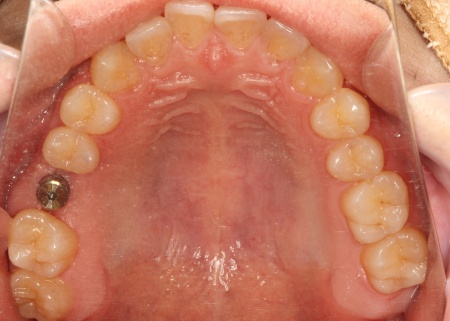

20代男性 割れた奥歯を抜いたあとインプラント治療を行った症例